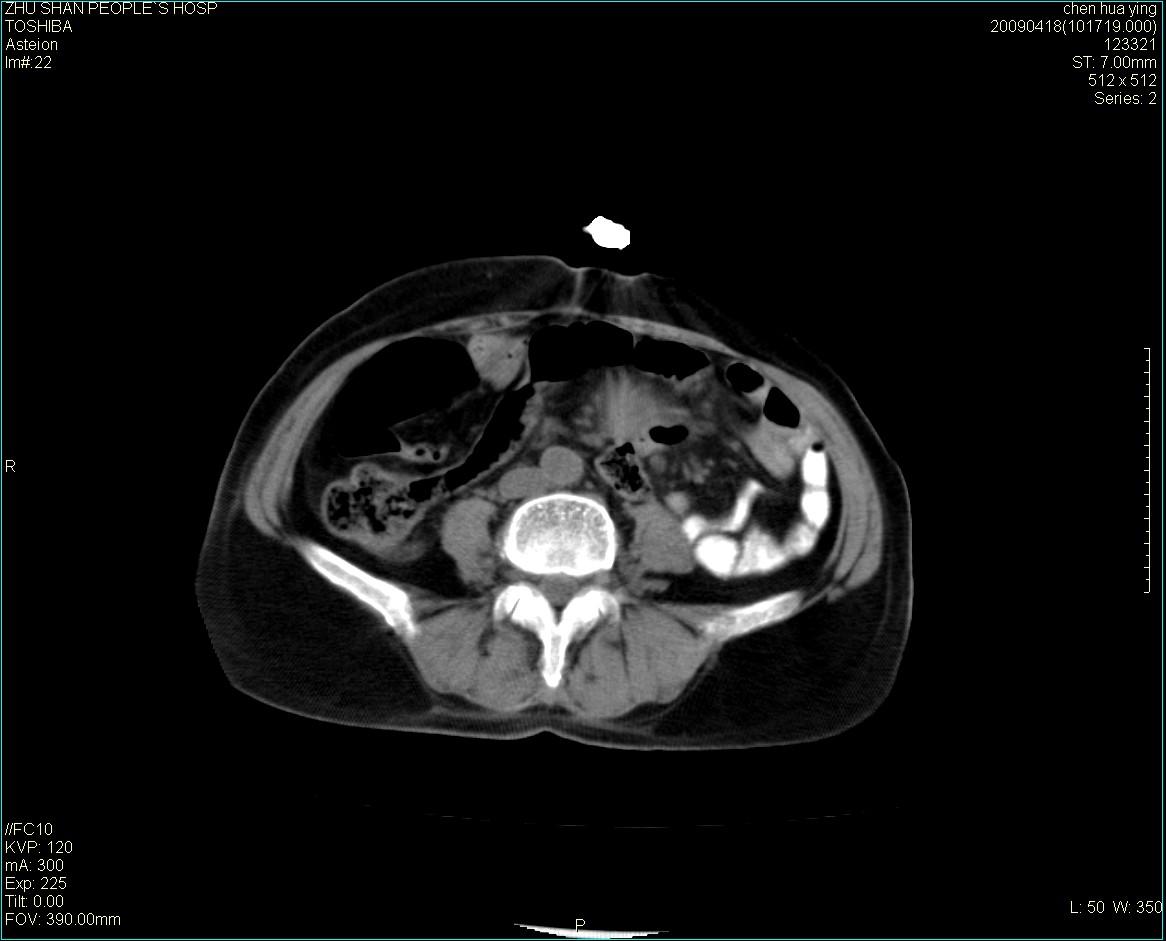

女性病人 65岁 腹部包块半年余结肠造影未见异常.

病灶略呈圆形有分叶状,上部层面呈实性,右侧见圆形低密度区,灶内见团块状钙化,病灶下方与肠管分境不清,考虑间质瘤可能性大,建议肠道准备后增强